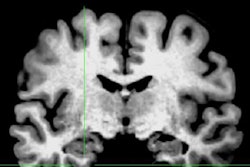

The researchers worked on the hypothesis that the inability of anterior temporal lobe resection to eliminate seizures in some patients with temporal lobe epilepsy had to do with tissue connected through networks to the lobe. While standard resection of the anterior temporal lobe can reduce the frequency of seizures, 30% to 50% of patients continue to experience seizures after surgery.

Chiang and colleagues used statistical techniques to analyze brain activity data from patients with epilepsy and from groups of healthy controls. They found that the recurrence of seizures after surgery may be due to surgical disruption of fibers connected to previously normal brain tissue or incomplete resection of an epileptogenic network.